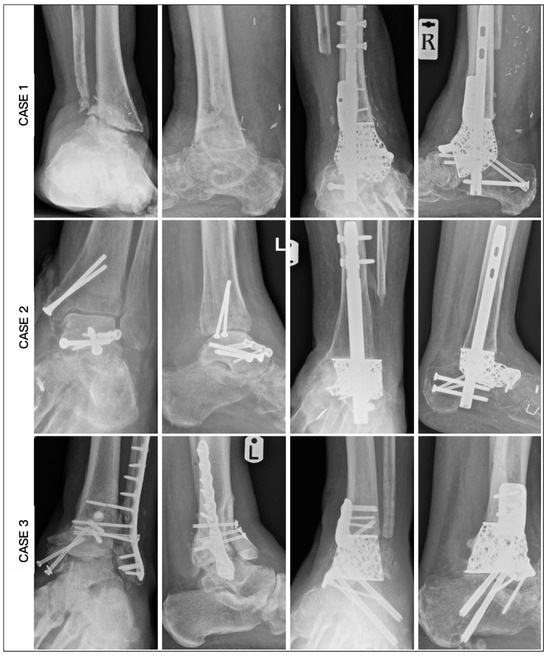

| CASE | 1 | 2 | 3 | 4 | 5 | 6 |

|---|---|---|---|---|---|---|

| Age | 62 | 59 | 60 | 60 | 78 | 67 |

| Diagnosis | OM | OM | OM | AVN | AVN | AVN |

| Smoking | No | Yes | Yes | No | Yes | No |

| BMI | 26.5 | 27.4 | 27.4 | 28.2 | 32.1 | 35.4 |

| Medical | Nil | IHD, CKD, PAD | CKD | CKD, PAD | DM | IHD, DM, CKD, CN |

| HbA1c | 36 | 39 | 39 | 41 | 49 | 70 |

| CRP | 8 | 7 | 16 | 9 | 10 | 6 |

| Hb (g/L) | 113 | 105 | 132 | 146 | 113 | 114 |

| Past surgery | 5 | 3 | 3 | 0 | 1 | 0 |

| Modification | Tibial and Navicular Flange, Nail | Navicular Flange, Nail | Tibial and Navicular Flange | Navicular Flange, Nail | Nail | Articulating Navicular Extension, Tibial Flange, Nail |

| Duration of surgery (min) | 255 | 220 | 162 | 210 | 190 | 205 |

| Wound Healing (days) | 42 | 40 | 20 | 29 | 32 | 45 |

| Union (weeks) | 25 | 19 | 16 | 14 | 27 | 20 |

| Ambulation (weeks) | 28 | 21 | 18 | 16 | 29 | 22 |